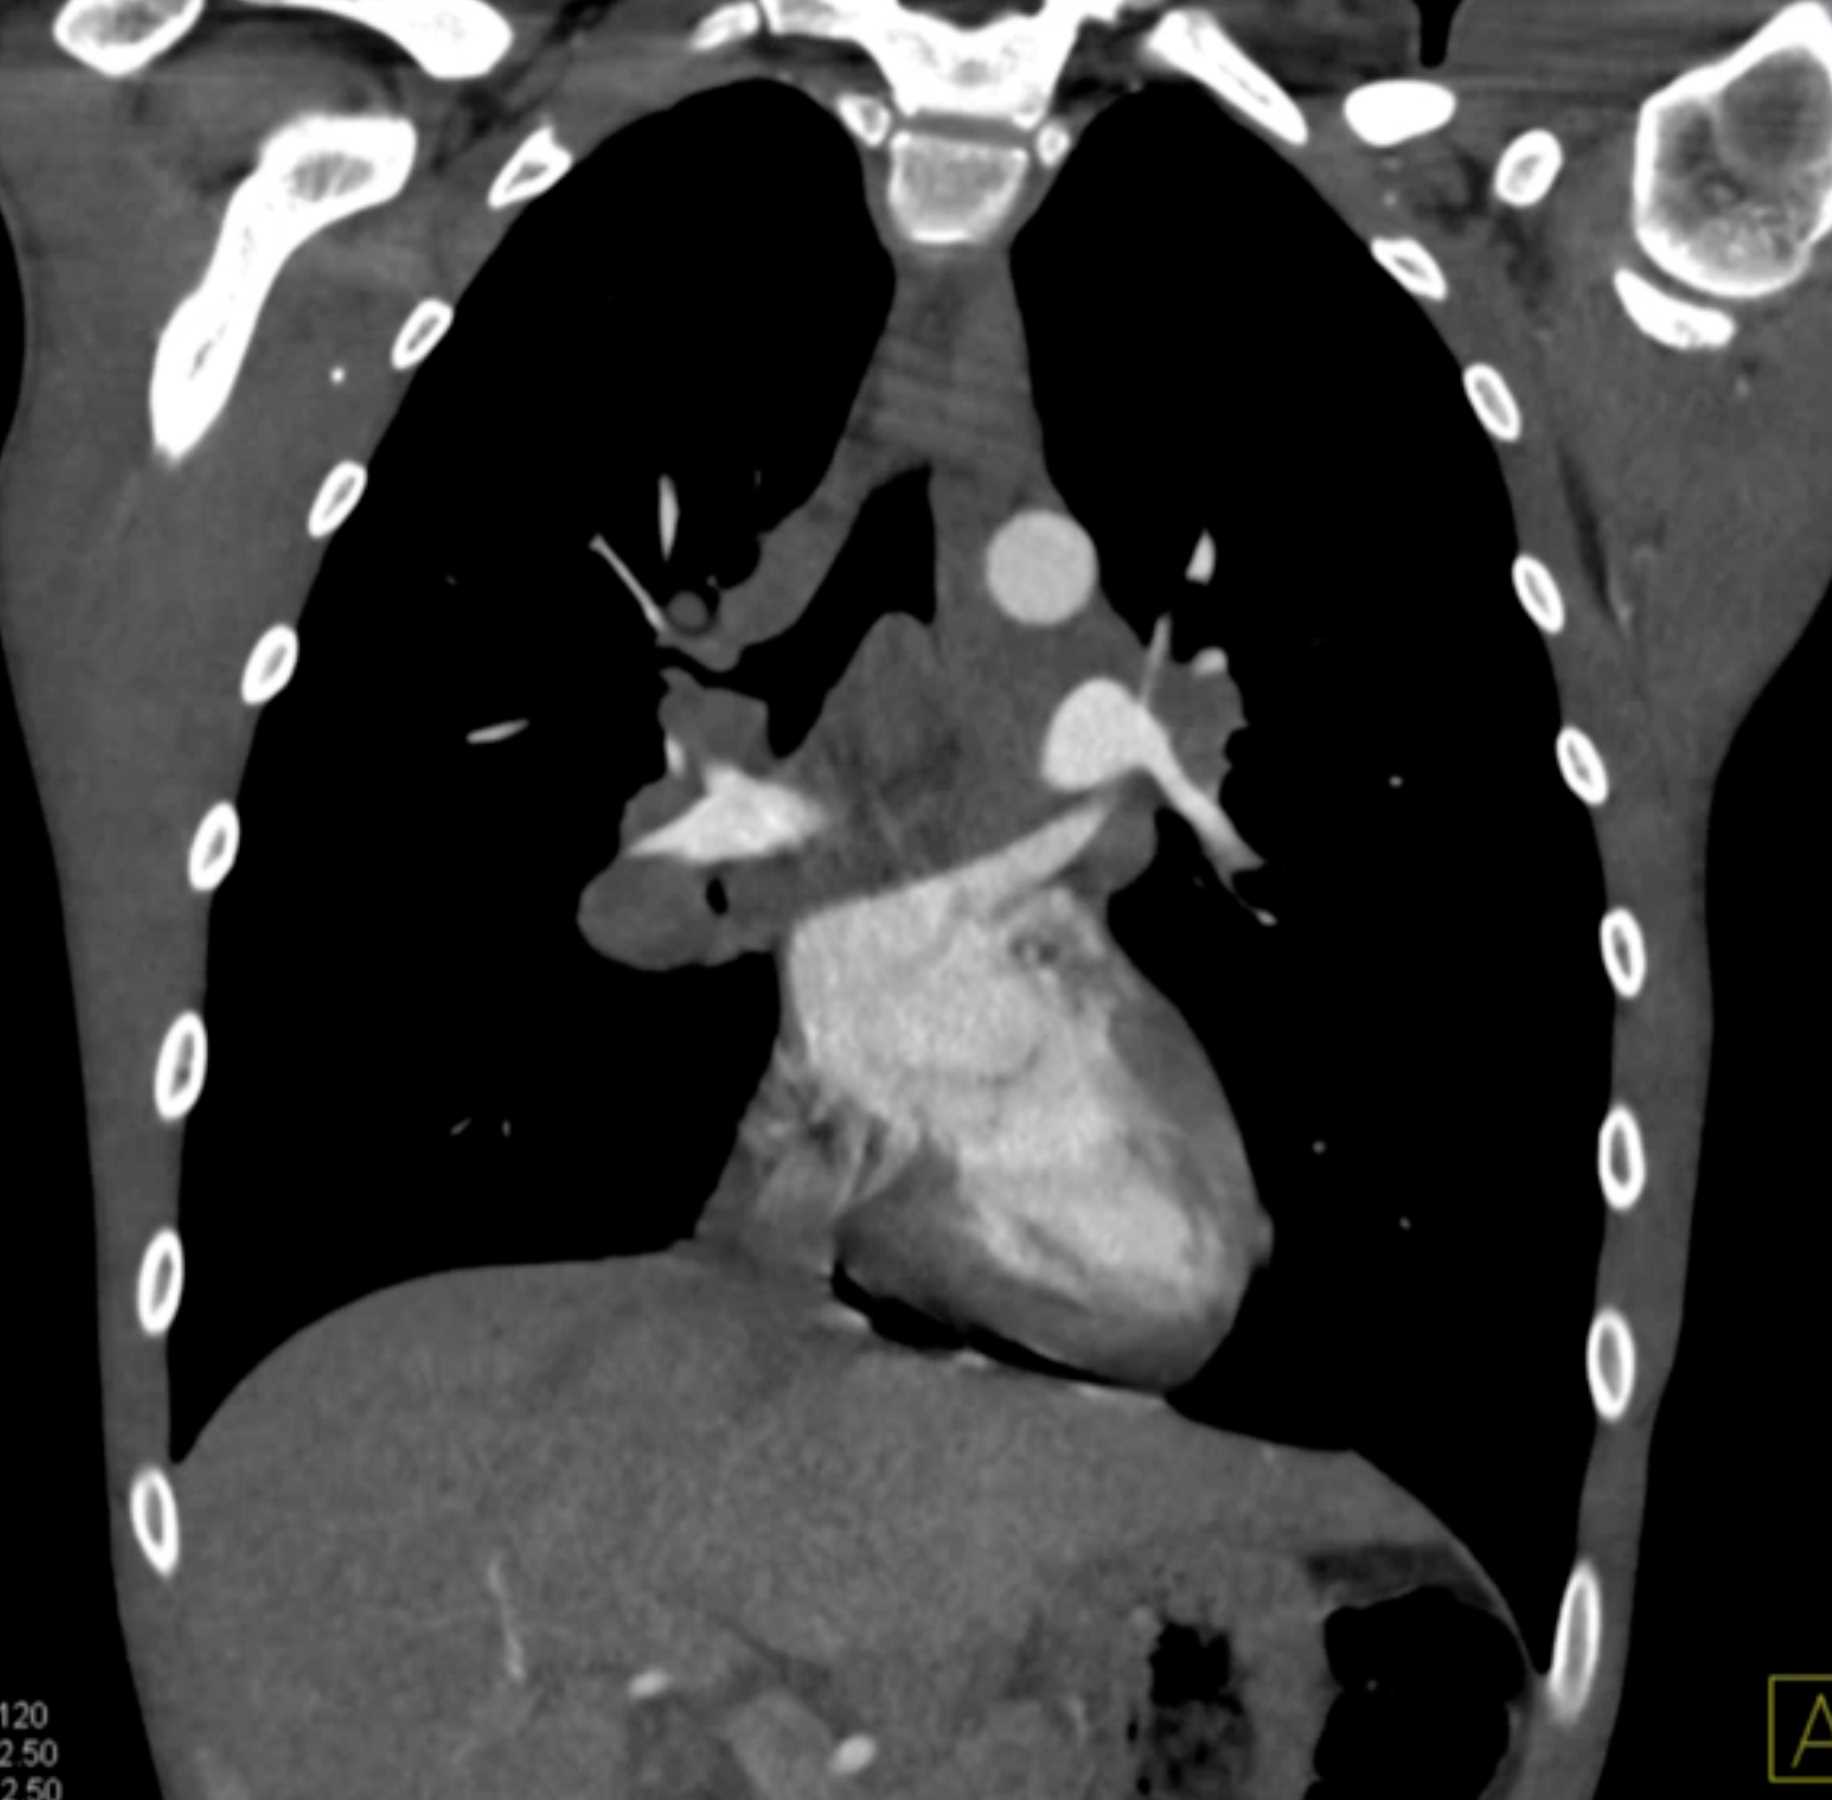

Large Cell Lymphoma